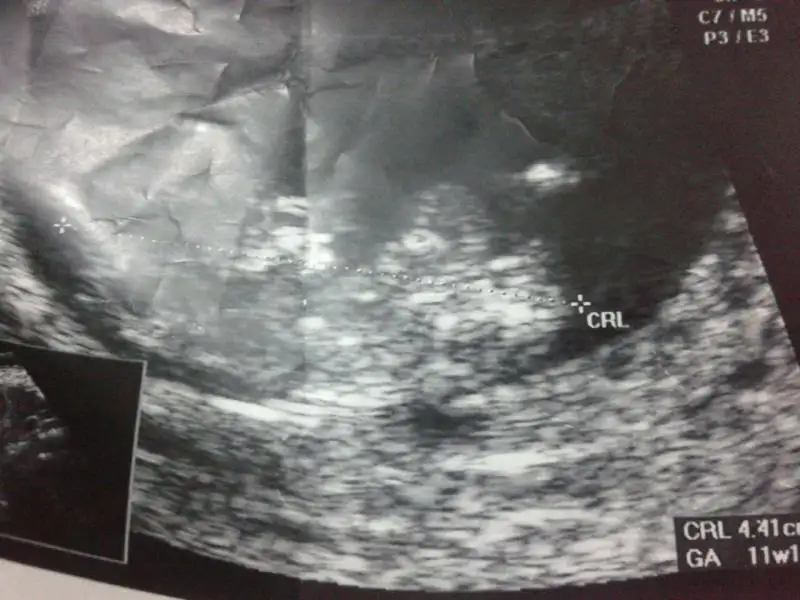

gönderdiğim resimleri yorumlarmısınız 11+1 günlük fotolar. şimdiden teşekkürederim

• $IMG-20140725-WA0001.webp

$IMG-20140725-WA0001.webp

26,1 KB · Görüntüleme: 99

• $IMG-20140725-WA0003.webp

$IMG-20140725-WA0003.webp

25,4 KB · Görüntüleme: 92